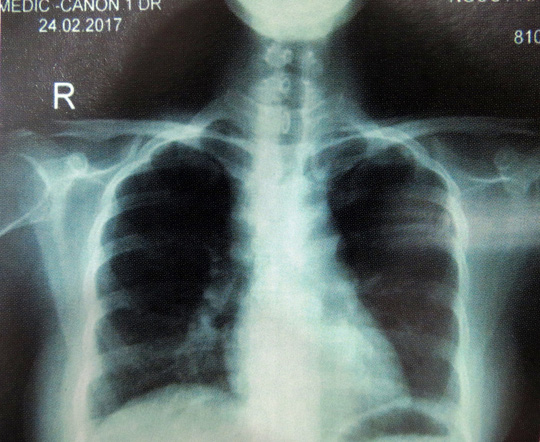

Đáng nói, sự nguy hiểm thực sự của căn bệnh không chỉ nằm trên da. Cô gái còn bị mờ mắt, chẩn đoán ban đầu là viêm màng bồ đào mắt mãn tính. Hai lá phổi cô cũng xuất hiện những nốt li ti, phì đại hạch rốn phổi phải và hạch trung thất. Tất cả các tổn thương tưởng không liên quan đó đều do bệnh siêu giả dạng gây ra.

Cụ thể, các triệu chứng về mắt của cô đã khỏi hoàn toàn, các hạch rốn phổi phải và hạch trung thất giảm kích thước đáng kể. Riêng các tổn thương về da có những đợt giảm rồi tái phát, đến nay đã giảm gần hết và các bác sĩ hy vọng nó sẽ sớm biến mất hẳn. Hiện cô tiếp tục được điều trị nội khoa với thuốc liều nhẹ.